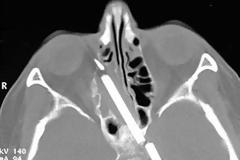

Απίστευτο και όμως, αληθινό. Ένας νεαρός άνδρας ζούσε επί 15 έτη με ένα μολύβι σφηνωμένο στο κεφάλι του